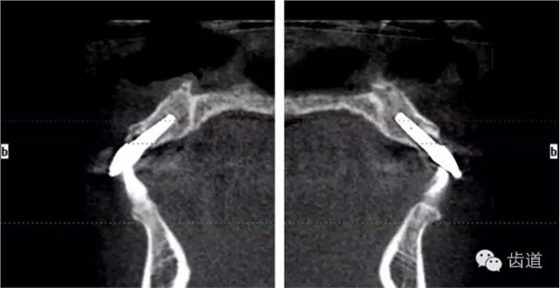

術(shù)前放射片

術(shù)后CT

戴牙后CT